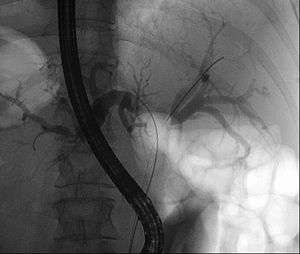

| Klatskin tumor during ERCP. In the left and right biliary system wires were placed. Both parts were injected through a tube with contrast. The lack of contrast in the area of the confluence is clearly visible. | |